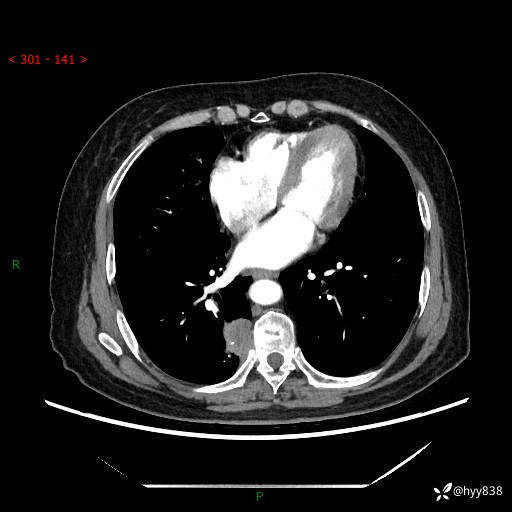

增强动脉期+静脉期

两期CT值:55Hu 53hu